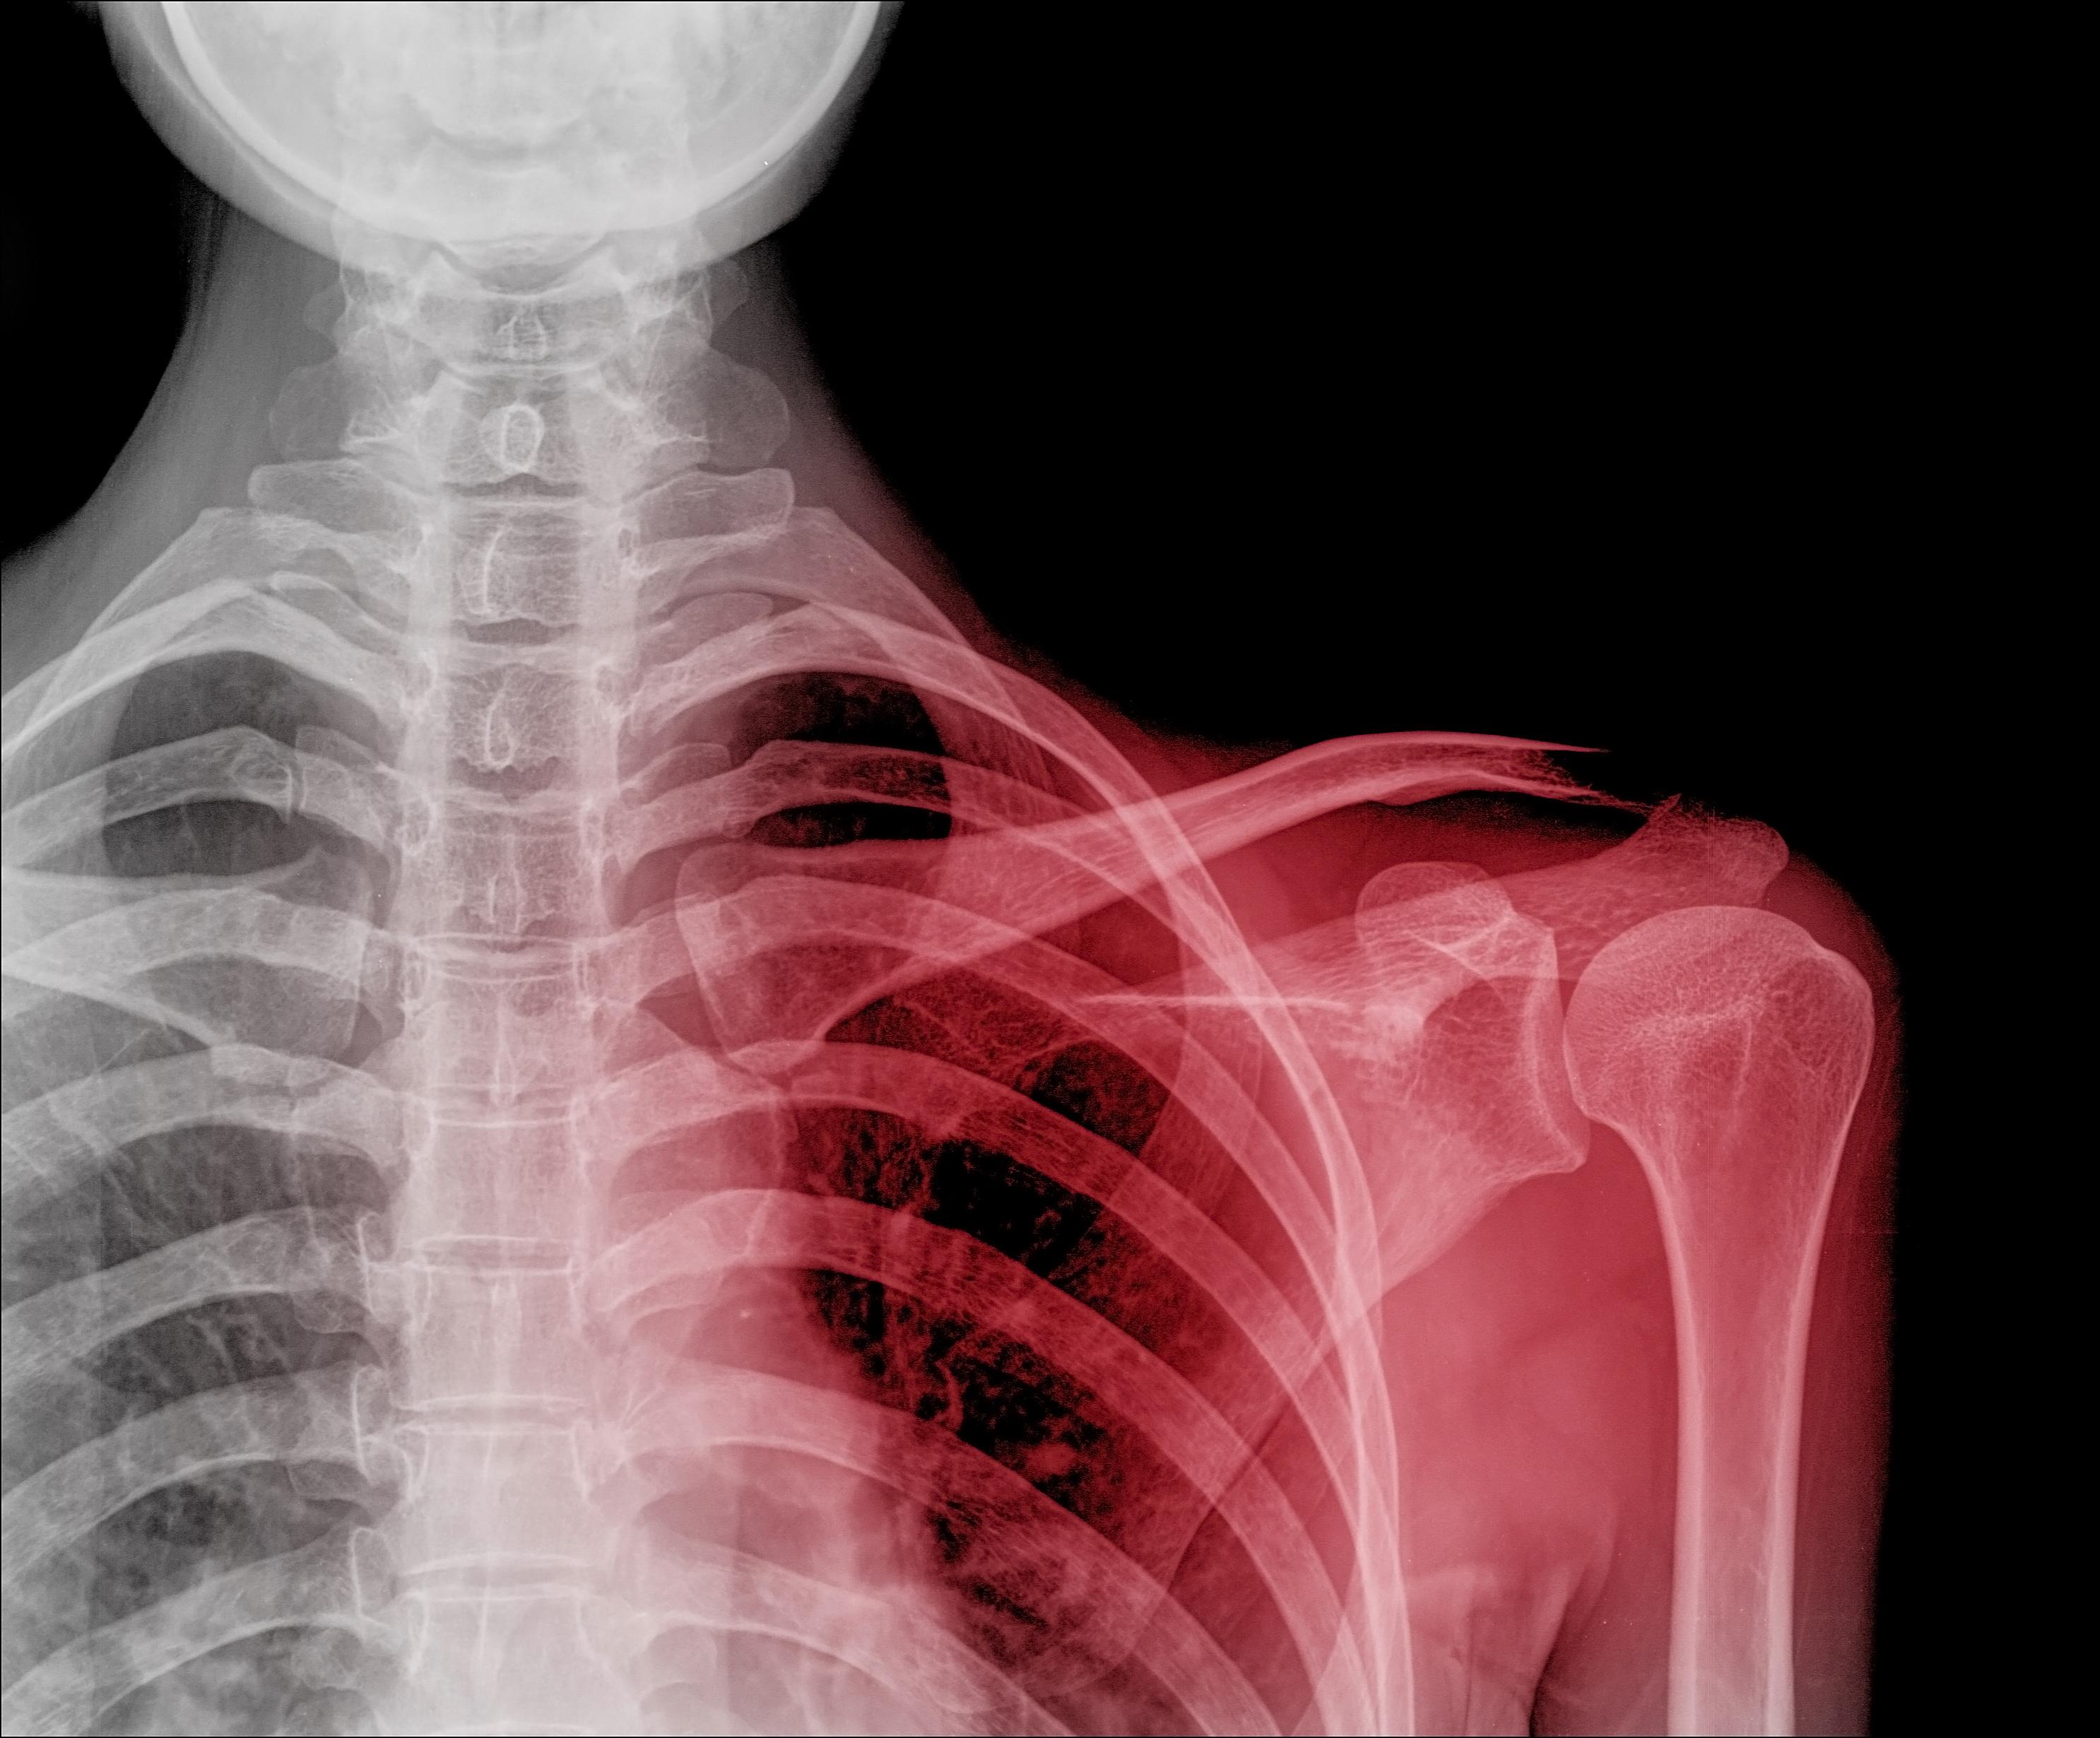

Çıkıklar, bir eklemi oluşturan kemiklerin normal hizalarından saparak birbirinden ayrılması durumudur. Bu, genellikle eklemi çevreleyen bağların, tendonların veya kapsülün hasar görmesiyle meydana gelir. Çıkıklar, çoğu zaman travmatik bir olay sonucu ortaya çıkar; örneğin bir düşme, trafik kazası veya spor sırasında yaşanan bir darbe bu duruma neden olabilir. Vücudun en sık etkilenen bölgeleri arasında omuz, dirsek, parmaklar ve kalça yer alır. Peki, bu durum neden bu kadar önemlidir? Çünkü doğru ve hızlı bir müdahale yapılmadığında, sinir hasarı veya dolaşım problemleri gibi ciddi komplikasyonlar gelişebilir.

- Deformasyon: Eklemin normal görünümünde bir bozulma fark edilebilir. Örneğin, omuz çıkığı durumunda omuzun şekli anormal görünebilir.